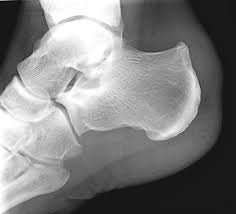

Haglund’s deformity

A bony prominence at the back of the heel

Can worsen insertional Achilles pain

Symptoms may be aggravated by stiff-backed footwear

Occurs where the tendon attaches to the heel bone

Often associated with bony irritation at the heel